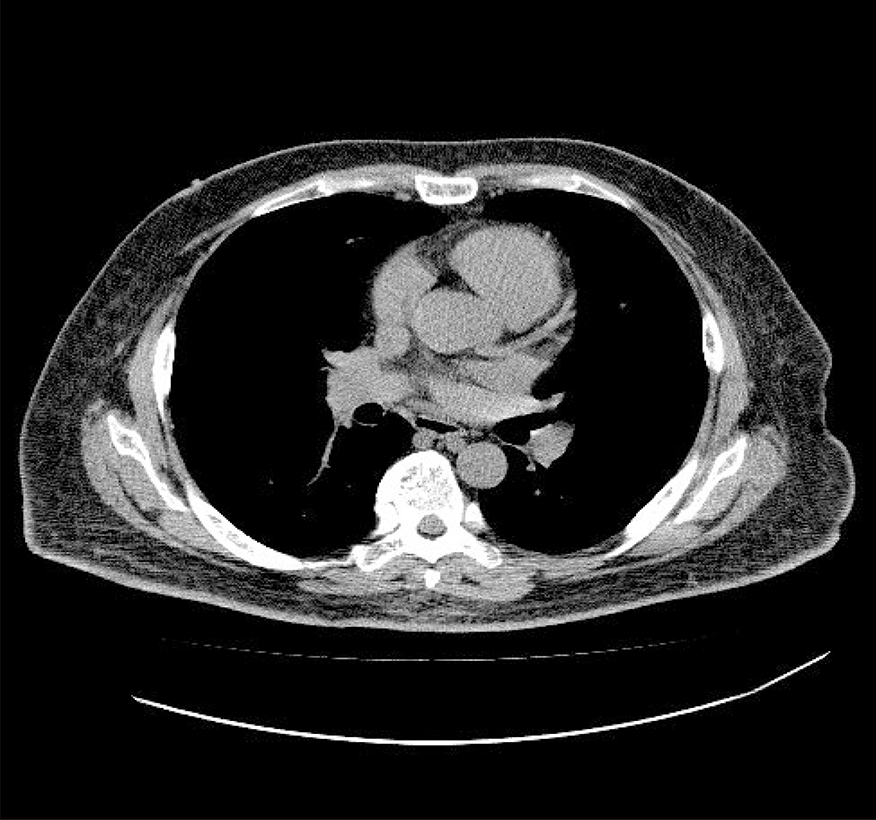

・冠動脈疾患(冠動脈石灰化病変)

心臓を栄養する血管である冠動脈の石灰化を測定するCT検査です。

胸部CTより少ない被ばく線量で造影剤を使わず、比較的簡便に心筋梗塞や狭心症のリスクを調べられる検査です。

冠動脈の石灰化は動脈硬化が進行し、血管の壁にカルシウムが沈着した状態です。石灰化が多いほど動脈硬化が進み心筋梗塞や狭心症のリスクが高くなります。

石灰化スコアCTで血管の状態を調べてみましょう。

石灰化が認められない血管

石灰化が認められる血管